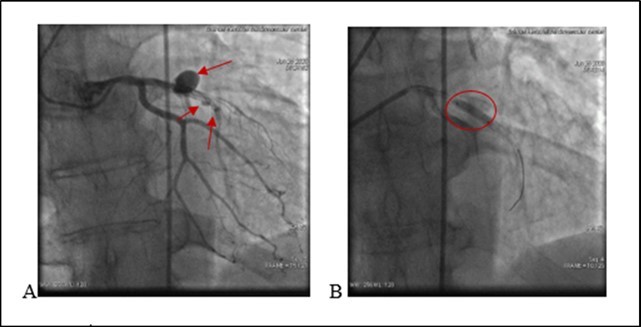

On ECG : HR 78 . Sinus rythm. ST segment elevation I, aVL, V1- V5 (2mm at the J-point). Q wave in V2-V4 leads. T/A 180/70 mm Hg. Patient refused missing of presribed medications. Due to severe chest pain, ECG data and haemodynamic instability an urgent PCI was performed. It revealed a stent thrombosis in LAD - early stent thombosis (1). Circumflex Coronary artery (CX) and Right Coronary artery (RCA)- without significant changes (see Figure 2).

Figure 2.(20.06.2020) .A. Occluded stent due to early thrombosis (red arrow). B.C Balloon angioplasty and stenting. D. Final result.

(20.06.2020) .A. Occluded stent due to early thrombosis (red arrow). B.C Balloon angioplasty and stenting. D. Final result.

After administration of a 180 mg loading dose of ticagrelor and an intravenous bolus of 10.000 units heparin, left main coronary artery was cannulated with a 6F EXB4 guiding catheter and a 0.014’’ floppy guide wire was advanced in LAD. Coronary artery recanalisation performed successfully. After baloon angioplasty with 3.0X12 mm baloon-catheter, in proximal and medial segments intraluminal filling defect was observed – reduced contrast dencity and heziness and two BMS were overlaped - 3.5X24 mm and 3.0X24 mm respectively. Postdilation was performed at the end of the procedure.TIMI score was 3. Procedure performed without any techincal complication during coronary intervention. Patient was stable and he was transferred to the Intensive Care Unit.